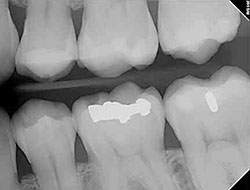

x-rayUsing the most advanced dental technology possible is just as important as staying up-to-date on the latest treatment techniques. Because our practice is dedicated to providing you with the safest and most convenient treatment options available, we utilize advanced digital X-ray technology in our office.

Digital X-rays provide several advanced imaging options that are designed to save time, provide clearer dental photos, and expose patients to less radiation than with traditional X-ray technology.

Our practice is focused on making your dental experience as comfortable as possible. At your next appointment, we’ll be happy to answer any questions you may have.